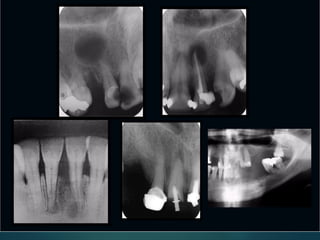

Clasificación Radiográfica

De Las Caries

Incipiente de esmalte

De esmalte

Dentinaria superficial

Dentinaria profunda

Sobreproyectada en cámara pulpar

Penetrante